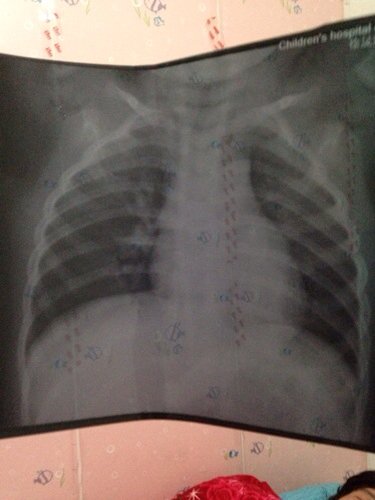

宝宝拍片支气管肺炎 医生叫我家打针 我不舍得 开点药 开的药是川贝散 止咳口服液 还有中医贴穴位的 宝宝拍片支气管肺炎。医生叫我家打针。我不舍得。开点药。开的药是川贝散。止咳口服液。还有中医贴穴位的。他说支气管肺炎。但是开的都说止咳的药 以下图片。请帮忙看看 孩子严不严重 点击展开 匿名用户 2014-01-04 17:33 为您推荐: 其他回答 病情分析: 你好,单看这张片子不是很严重。 指导意见: 病情轻重要综合考虑,结合检查和病史,肺部听诊一起决定。 匿名用户 2014-01-04 20:11 相关问题 蛇胆川贝止咳糖浆治疗小孩支气管肺炎吗孩子半夜咳的厉害我该怎么办? 宝宝现在支气管肺炎我不可以喝奶全部喂梨水他会饿着吗?家里天天吃雪梨炖川贝希望他多喝水,宝宝三个月大喝奶粉的 两岁宝宝支气管肺炎打了11天针,打针期间